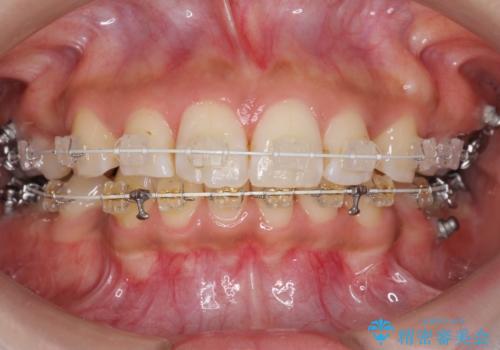

- 矯正装置

- 審美装置

- 前歯を下げたいと来院。

初めは、上だけ抜歯しましたが、もう少し口元を下げたいとのことで追加で下顎を抜歯しました。

年齢の割に歯が動きにくかったこともあり、また、追加で抜歯して結果として時間がかかってしまいました。口元が大きく下がり、結果には満足していただけました。